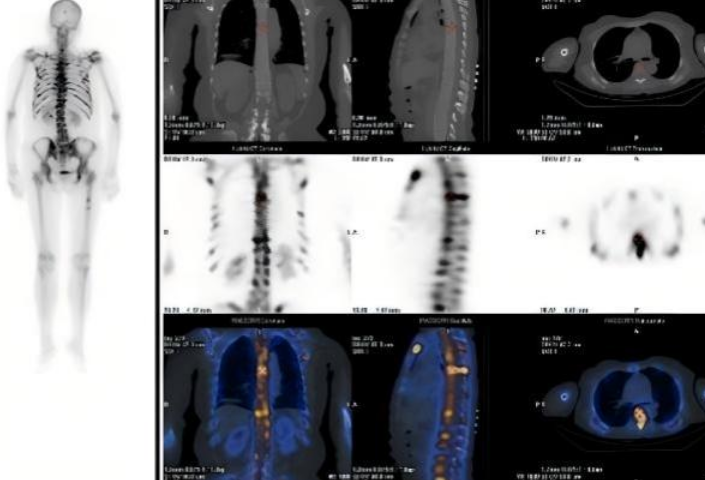

患者因不明原因发热、剧烈骨痛伴体重骤降前来就诊。入院后,全腹及胸部CT未见明显异常,但血常规提示白细胞、淋巴细胞、血小板及红细胞计数均显著降低。为进一步探明病因,临床医生安排了全身骨扫描(SPECT/CT),结果显示全身多处骨骼放射性浓聚,初步怀疑为肿瘤骨转移,其诊疗方向指向实体肿瘤,但其CT却未见明显病灶,诊断陷入了困境。临床医生随即安排可以全身扫描尤其对肿瘤病变尤为敏感的PET-CT检查。

患者全身骨扫描(SPECT/CT)核医学显像图。

经PET-CT检查,患者全身骨弥漫性明显代谢增高,其他脏器均并未找到明确的实体原发灶,这样的显像结果推翻了肿瘤骨转移的初步诊断。核医学科医生看到这样的显像结果,并结合患者的临床表现,一个新的诊断方向在脑海中回荡:淋巴瘤?血液系统疾病?按照这一方向,为患者进一步进行了骨髓穿刺等检查,终于这个凶手被找到——急性淋巴细胞白血病。

患者PET-CT的显像图。

急性淋巴细胞白血病是一种起源于淋巴细胞的恶性肿瘤,其异常增生的白血病细胞会浸润全身骨骼和骨髓,破坏骨代谢平衡,导致骨骼出现弥漫性代谢活跃和浓聚表现。这正是患者在PET-CT和骨扫描上出现异常浓聚的原因。同时,患者持续发热、体重骤降等症状,也是白血病细胞大量增殖、释放致热原并抑制机体正常免疫功能的典型表现。